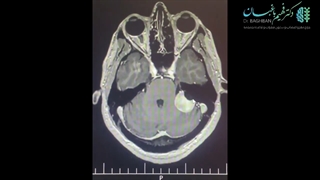

عمل جراحی شوانوم در ناحیه ی سی پی انگل و حفره ی میانی جمجمه